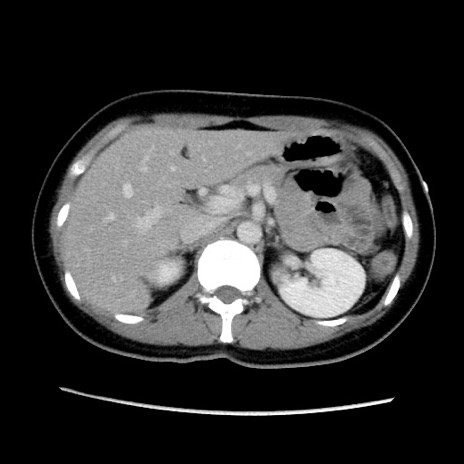

症例39(横断像)

【症例】40歳代女性

【主訴】上下腹部痛

【現病歴】2日目から下腹部痛あり。夜間は痛みで眠れなかった。昨日より上腹部痛と下痢が出現。臥位で痛みは軽快したため、休んでいた。本日になって臥位でも立位でも痛みが強くなってきたため救急要請。

【既往歴】子宮内膜症

【身体所見】部:平坦・軟、左上下腹部に圧痛あり、反跳痛あり。

【データ】WBC 21800、CRP 26.78